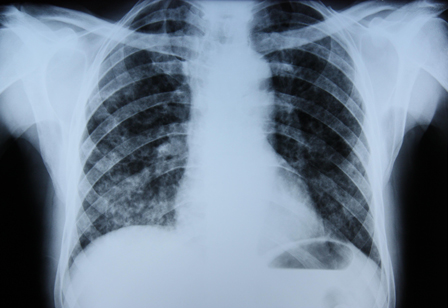

Chest x-ray

A chest x-ray should be obtained early in the evaluation of chronic cough.[38] Although it is not diagnostic of the most common causes, findings may quickly divert the evaluation to causes of greater gravity, such as structural lung diseases. These include lung cancer, pulmonary fibrosis, tuberculosis, bronchiectasis, pneumonia, aspiration, and sarcoidosis.[Figure caption and citation for the preceding image starts]: Chest x-ray showing hyperinflation in a patient with COPD. The hyperinflation is caused by the emphysema component of COPD, rather than the chronic bronchitis that underlies symptoms of coughFrom the personal collection of Dr M. A. Sharifabadand, SUNY at Stony Brook School of Medicine, Department of Pulmonary and Critical Care Medicine, Mineola, New York and Dr J. P. Parsons, The Ohio State University Medical Center, Columbus; used with permission [Citation ends].com.bmj.content.model.assessment.Caption@65a65855[Figure caption and citation for the preceding image starts]: Chest x-ray showing multiple miliary lung metastases (arrows). The primary tumour was a thyroid carcinomaE. Dick, Student BMJ. 2001;9:10-12 [Citation ends].com.bmj.content.model.assessment.Caption@25657fee[Figure caption and citation for the preceding image starts]: Chest x-ray showing left hilar carcinoma (arrow)From: E. Dick, Student BMJ. 2000;8:358-360 [Citation ends].com.bmj.content.model.assessment.Caption@567b9fef[Figure caption and citation for the preceding image starts]: Chest x-ray showing a cavitating right hilar carcinoma (arrow)E. Dick, Student BMJ. 2001;9:10-12 [Citation ends].com.bmj.content.model.assessment.Caption@3d6fa55[Figure caption and citation for the preceding image starts]: Chest x-ray in a patient with bronchogenic carcinoma showing a left-sided pleural effusionFrom: R. Thakkar, Student BMJ. 2001;9:458 [Citation ends].com.bmj.content.model.assessment.Caption@5b46acec[Figure caption and citation for the preceding image starts]: Chest x-ray showing interstitial fibrosis in a patient with amiodarone pulmonary toxicityFrom the personal collection of Dr A. Pataka and Professor P. Argyropoulou, Aristotle University, Thessaloniki, Greece; used with permission [Citation ends].com.bmj.content.model.assessment.Caption@2c3c94b0[Figure caption and citation for the preceding image starts]: Chest x-ray showing pulmonary tuberculosis with cavitationFrom the personal collection of Dr M. Narita, Department of Pulmonary and Critical Care Medicine, University of Washington [Citation ends].com.bmj.content.model.assessment.Caption@3dd7f84b[Figure caption and citation for the preceding image starts]: Chest x-ray showing multiple discrete nodules throughout both lungs (one of which is circled) in a patient with miliary tuberculosisE. Dick, Student BMJ. 2001;9:10-12 [Citation ends].com.bmj.content.model.assessment.Caption@23fa6365[Figure caption and citation for the preceding image starts]: Chest x-ray with lack of normal tapering producing a tram line in a patient with bronchiectasisFrom the personal collection of Dr S.M. Bhorade, University of Chicago Medical Center; used with permission [Citation ends].com.bmj.content.model.assessment.Caption@36b415f2[Figure caption and citation for the preceding image starts]: Chest x-ray with dilated and thickened airways in a patient with bronchiectasisFrom the personal collection of Dr S.M. Bhorade, University of Chicago Medical Center; used with permission [Citation ends].com.bmj.content.model.assessment.Caption@78e208fa[Figure caption and citation for the preceding image starts]: Chest x-ray showing increased opacification of the right perihilar region and superior segment of the right lower and upper lobes consistent with worsening aspiration pneumoniaFrom the personal collection of Dr R. Kanner, University of Utah School of Medicine [Citation ends].com.bmj.content.model.assessment.Caption@71be2c1f[Figure caption and citation for the preceding image starts]: Portable chest x-ray with bibasilar opacities, worse on the right than the left, in a patient with hospital-acquired pneumoniaFrom the personal collection of Dr F. W. Arnold, Division of Infectious Diseases, Department of Medicine, University of Louisville School of Medicine [Citation ends].com.bmj.content.model.assessment.Caption@2c704497[Figure caption and citation for the preceding image starts]: Chest x-ray showing early ill-defined opacities of the right upper lobe above the minor fissure consistent with early changes of aspiration pneumoniaFrom the personal collection of Dr R. Kanner, University of Utah School of Medicine [Citation ends].com.bmj.content.model.assessment.Caption@23fa54d0[Figure caption and citation for the preceding image starts]: A. Portable upright chest x-ray before aspiration; B. Chest x-ray 1 hour after aspiration, showing bilateral diffuse alveolar infiltrates, worse at the bases on the right sideFrom the personal collection of Dr S. Murgu and Dr H. Colt, University of California at Irvine Medical Center [Citation ends].com.bmj.content.model.assessment.Caption@7860be3a[Figure caption and citation for the preceding image starts]: Chest x-ray showing bilateral hilar adenopathy in a patient with sarcoidosisFrom the personal collection of Dr M.P. Muthiah, Division of Pulmonary and Critical Care and Sleep Medicine, University of Tennessee [Citation ends].com.bmj.content.model.assessment.Caption@31e94b4e